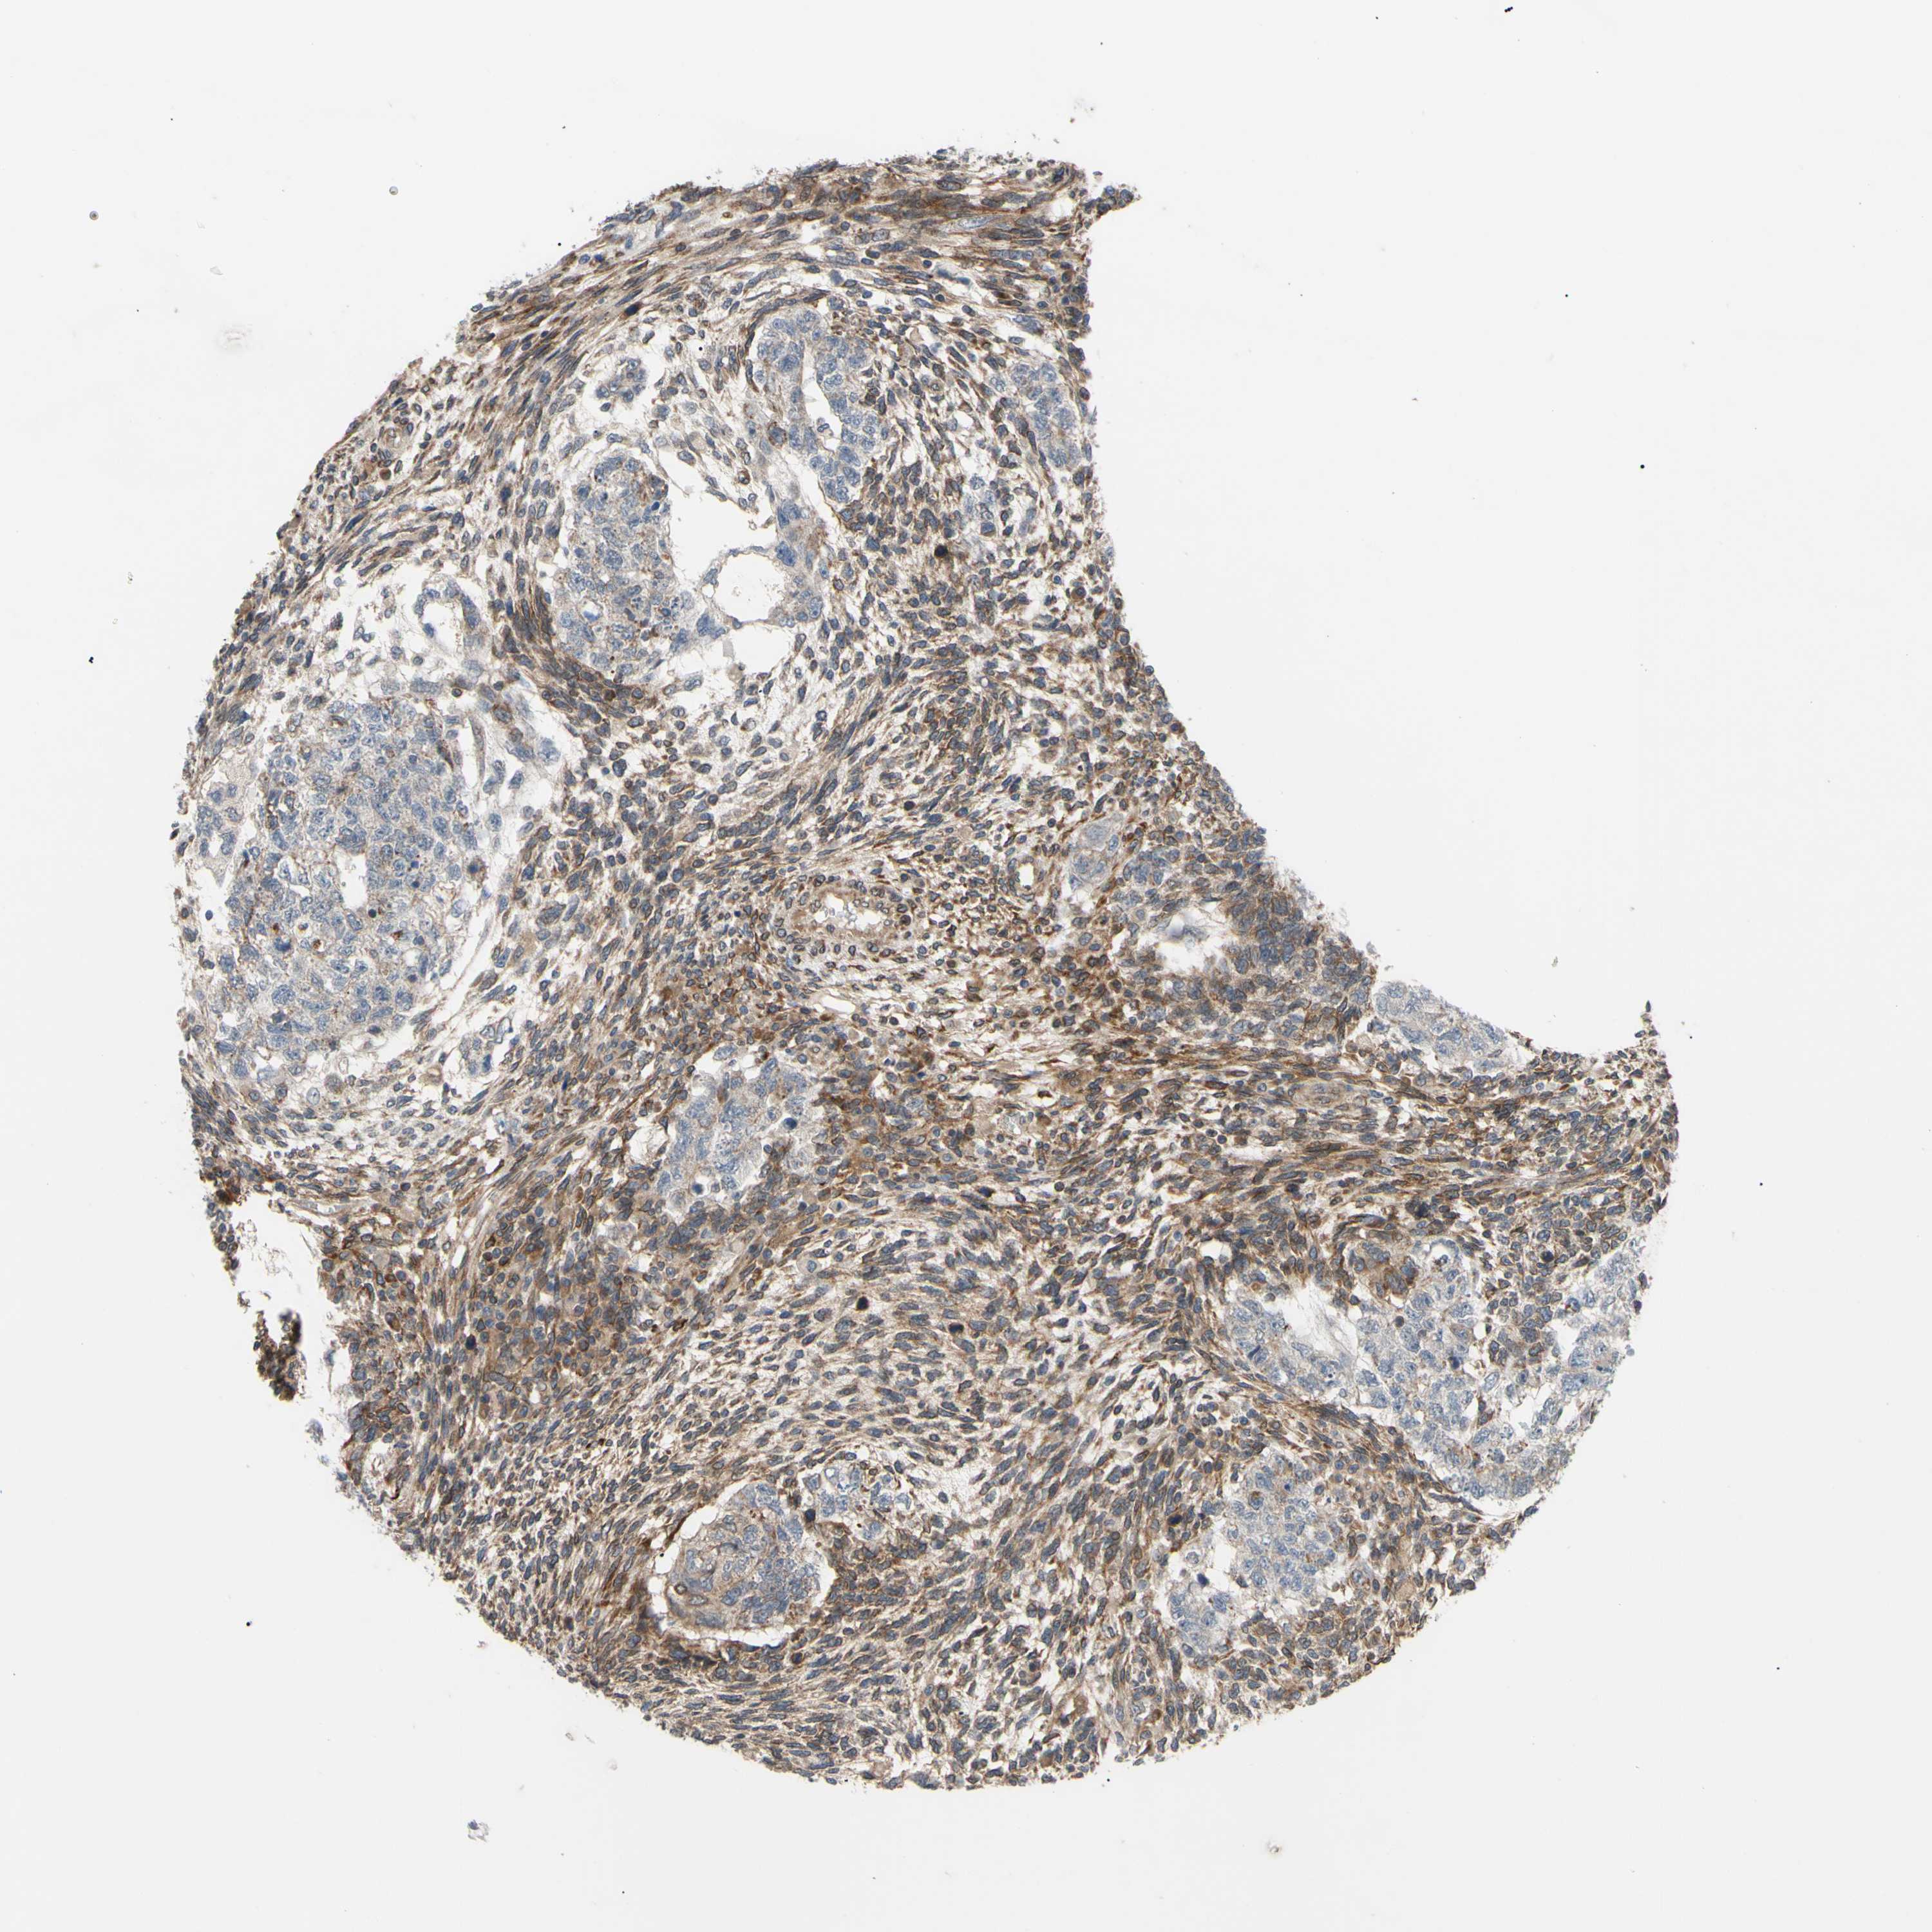

TESTIS CANCER - Protein expressioni

A mouse-over function shows sample information and annotation data. Click on an image to view it in a full screen mode. Samples can be filtered based on level of antibody staining by selecting one or several of the following categories: high, medium, low and not detected. The assay and annotation is described here.

Note that samples used for immunohistochemistry by the Human Protein Atlas do not correspond to samples in the TCGA dataset.

Antibody stainingi

Antibody staining in the annotated cell types in the current human tissue is reported as not detected, low, medium, or high, based on conventional immunohistochemistry profiling in selected tissues. This score is based on the combination of the staining intensity and fraction of stained cells.

Each image is clickable and will lead to virtual microscopy that enables deeper exploration of all samples and also displays staining intensity scores, fraction scores and subcellular localization as well as patient and tissue information for each sample.

Antibody CAB011655

Seminoma, NOS